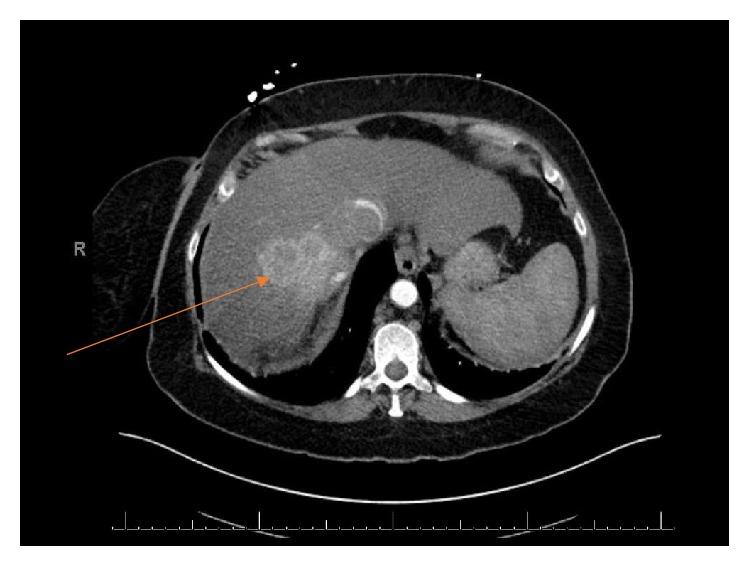

Renal cell carcinoma, particularly the most common clear cell type, is one of the most aggressive of urological cancers with significant risk of metastatic spread. It also has a propensity for venotropism with a proportion of tumors developing thrombi up to the right atrium. The response with newly adopted targeted therapy has been considered to be in the evolutionary stage with no clear role with respect to debulking or reducing the size of the inferior vena cava (IVC) thrombus. We describe a case of a right-sided metastatic RCC with Level IV thrombus initially managed with Pazopanib followed by Nivolumab and Adalimumab followed by cytoreductive nephrectomy and IVC thrombectomy in the post-targeted therapy setting with complete curative response.

肾细胞癌,尤其是最常见的透明细胞型,是侵袭性最强的泌尿系统癌症之一,具有显著的转移扩散风险。它还倾向于侵犯静脉,一部分肿瘤会形成血栓,甚至延伸至右心房。新采用的靶向治疗的疗效被认为尚处于发展阶段,对于减少下腔静脉(IVC)血栓的体积或清除血栓尚无明确作用。我们描述了一例右侧转移性肾细胞癌伴IV级血栓的病例,该病例最初采用帕唑帕尼治疗,随后使用纳武单抗和阿达木单抗,在靶向治疗后进行了减瘤性肾切除术和IVC血栓切除术,获得了完全治愈的效果。